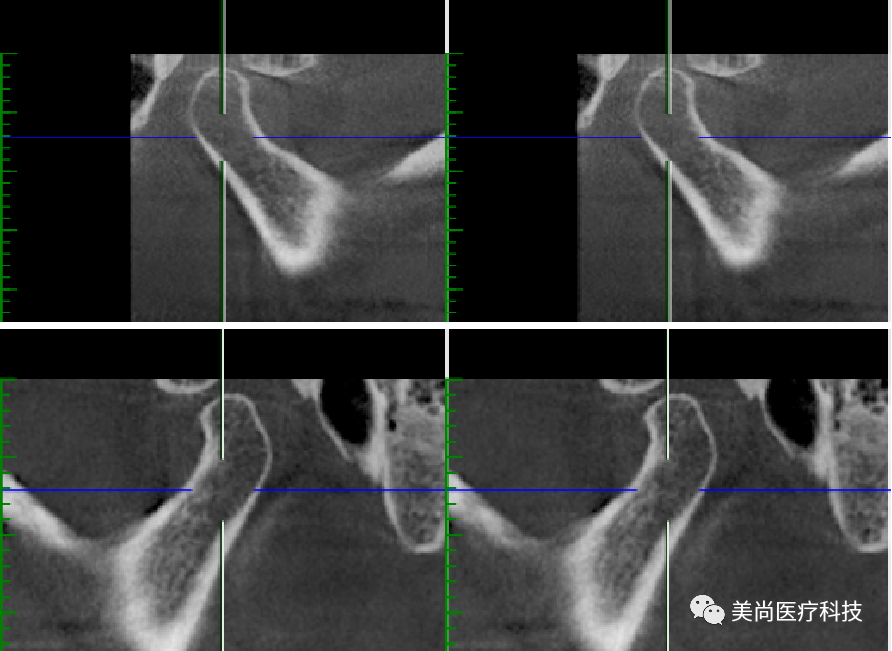

上颌可见烤瓷连桥修复Ⅲ°松动,牙龈微红肿;

下颌无牙颌附着龈狭窄仅1mm,牙槽嵴呈刀刃状;

32、42可用骨宽度6mm,可用骨高度10mm;

34、44可用骨宽度6mm,可用骨高度11.5mm。

导板下植入植体:

在32、42处植入3.5*10mm植体各一颗,植入扭矩约35n.cm;

在34、44处植入4.0*11.5mm植体各一颗,植入扭矩约40n.cm。